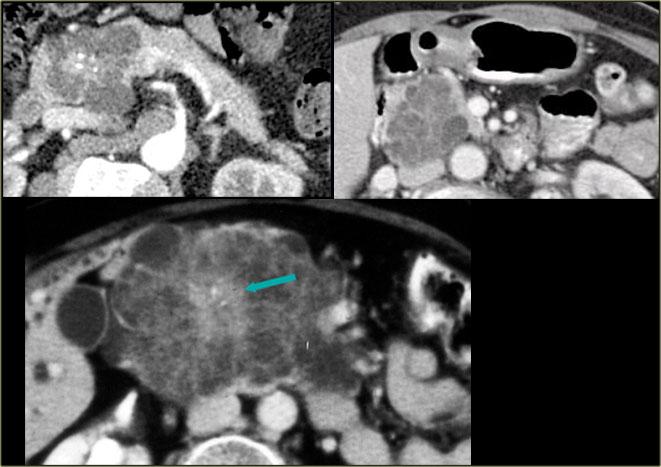

Hình ảnh CT của bệnh nhân nữ 51 tuổi có tiền sử sỏi mật và đau bụng.

Ghi nhận tổn thương giảm tỷ trọng với vôi hóa trung tâm ở đầu tụy.

Tổn thương có bờ viền thùy múi.

Tiếp tục xem hình ảnh MRI.

MRI thể hiện rõ hơn các đặc điểm hình thái của tổn thương (hình).

Trên chuỗi xung T2W, tổn thương có dạng đa nang.

Lưu ý vùng giảm tín hiệu trung tâm do sẹo trung tâm kèm vôi hóa.

Mặc dù một số nang có kích thước khá lớn, đây vẫn là hình ảnh đặc trưng của u nang tuyến thanh dịch (dạng đại nang).

Một ví dụ khác về u nang tuyến thanh dịch (Hình).

Hình ảnh sau tiêm thuốc cản quang bên phải cho thấy tổn thương giảm tỷ trọng với vôi hóa trung tâm ở thân tụy và ngấm thuốc nhẹ của các vách ngăn.

Lưu ý rằng trên CT rất khó nhận ra bản chất dạng nang của các tổn thương này và có thể nhầm lẫn với ung thư biểu mô tuyến tụy.

MRI sẽ dễ dàng thể hiện bản chất dạng nang của các tổn thương này (hình).

Chuỗi xung T2W với xóa mỡ (fatsat) thể hiện rõ tổn thương tăng tín hiệu dạng thùy múi với sẹo trung tâm, đây là hình ảnh đặc trưng của SCN.